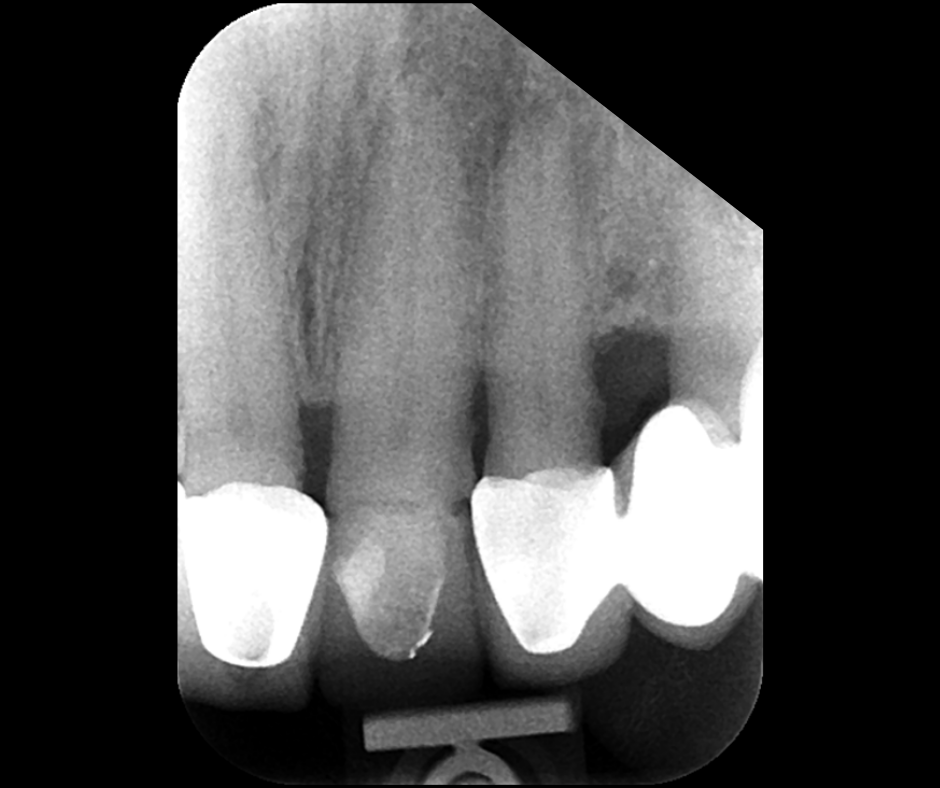

This course focuses on modern single-file endodontic systems, guiding participants through diagnosis, case assessment, access cavity design, canal location, root canal system preparation, and obturation techniques.

• To re-examine access cavity design and its importance in endodontic success

• To gain confidence in mechanical preparation using rotary and reciprocating NiTi shaping instruments

• To gain confidence in endodontic obturation and develop an understanding of various obturation techniques and methods of developing predictable, reproducible endodontic obturation